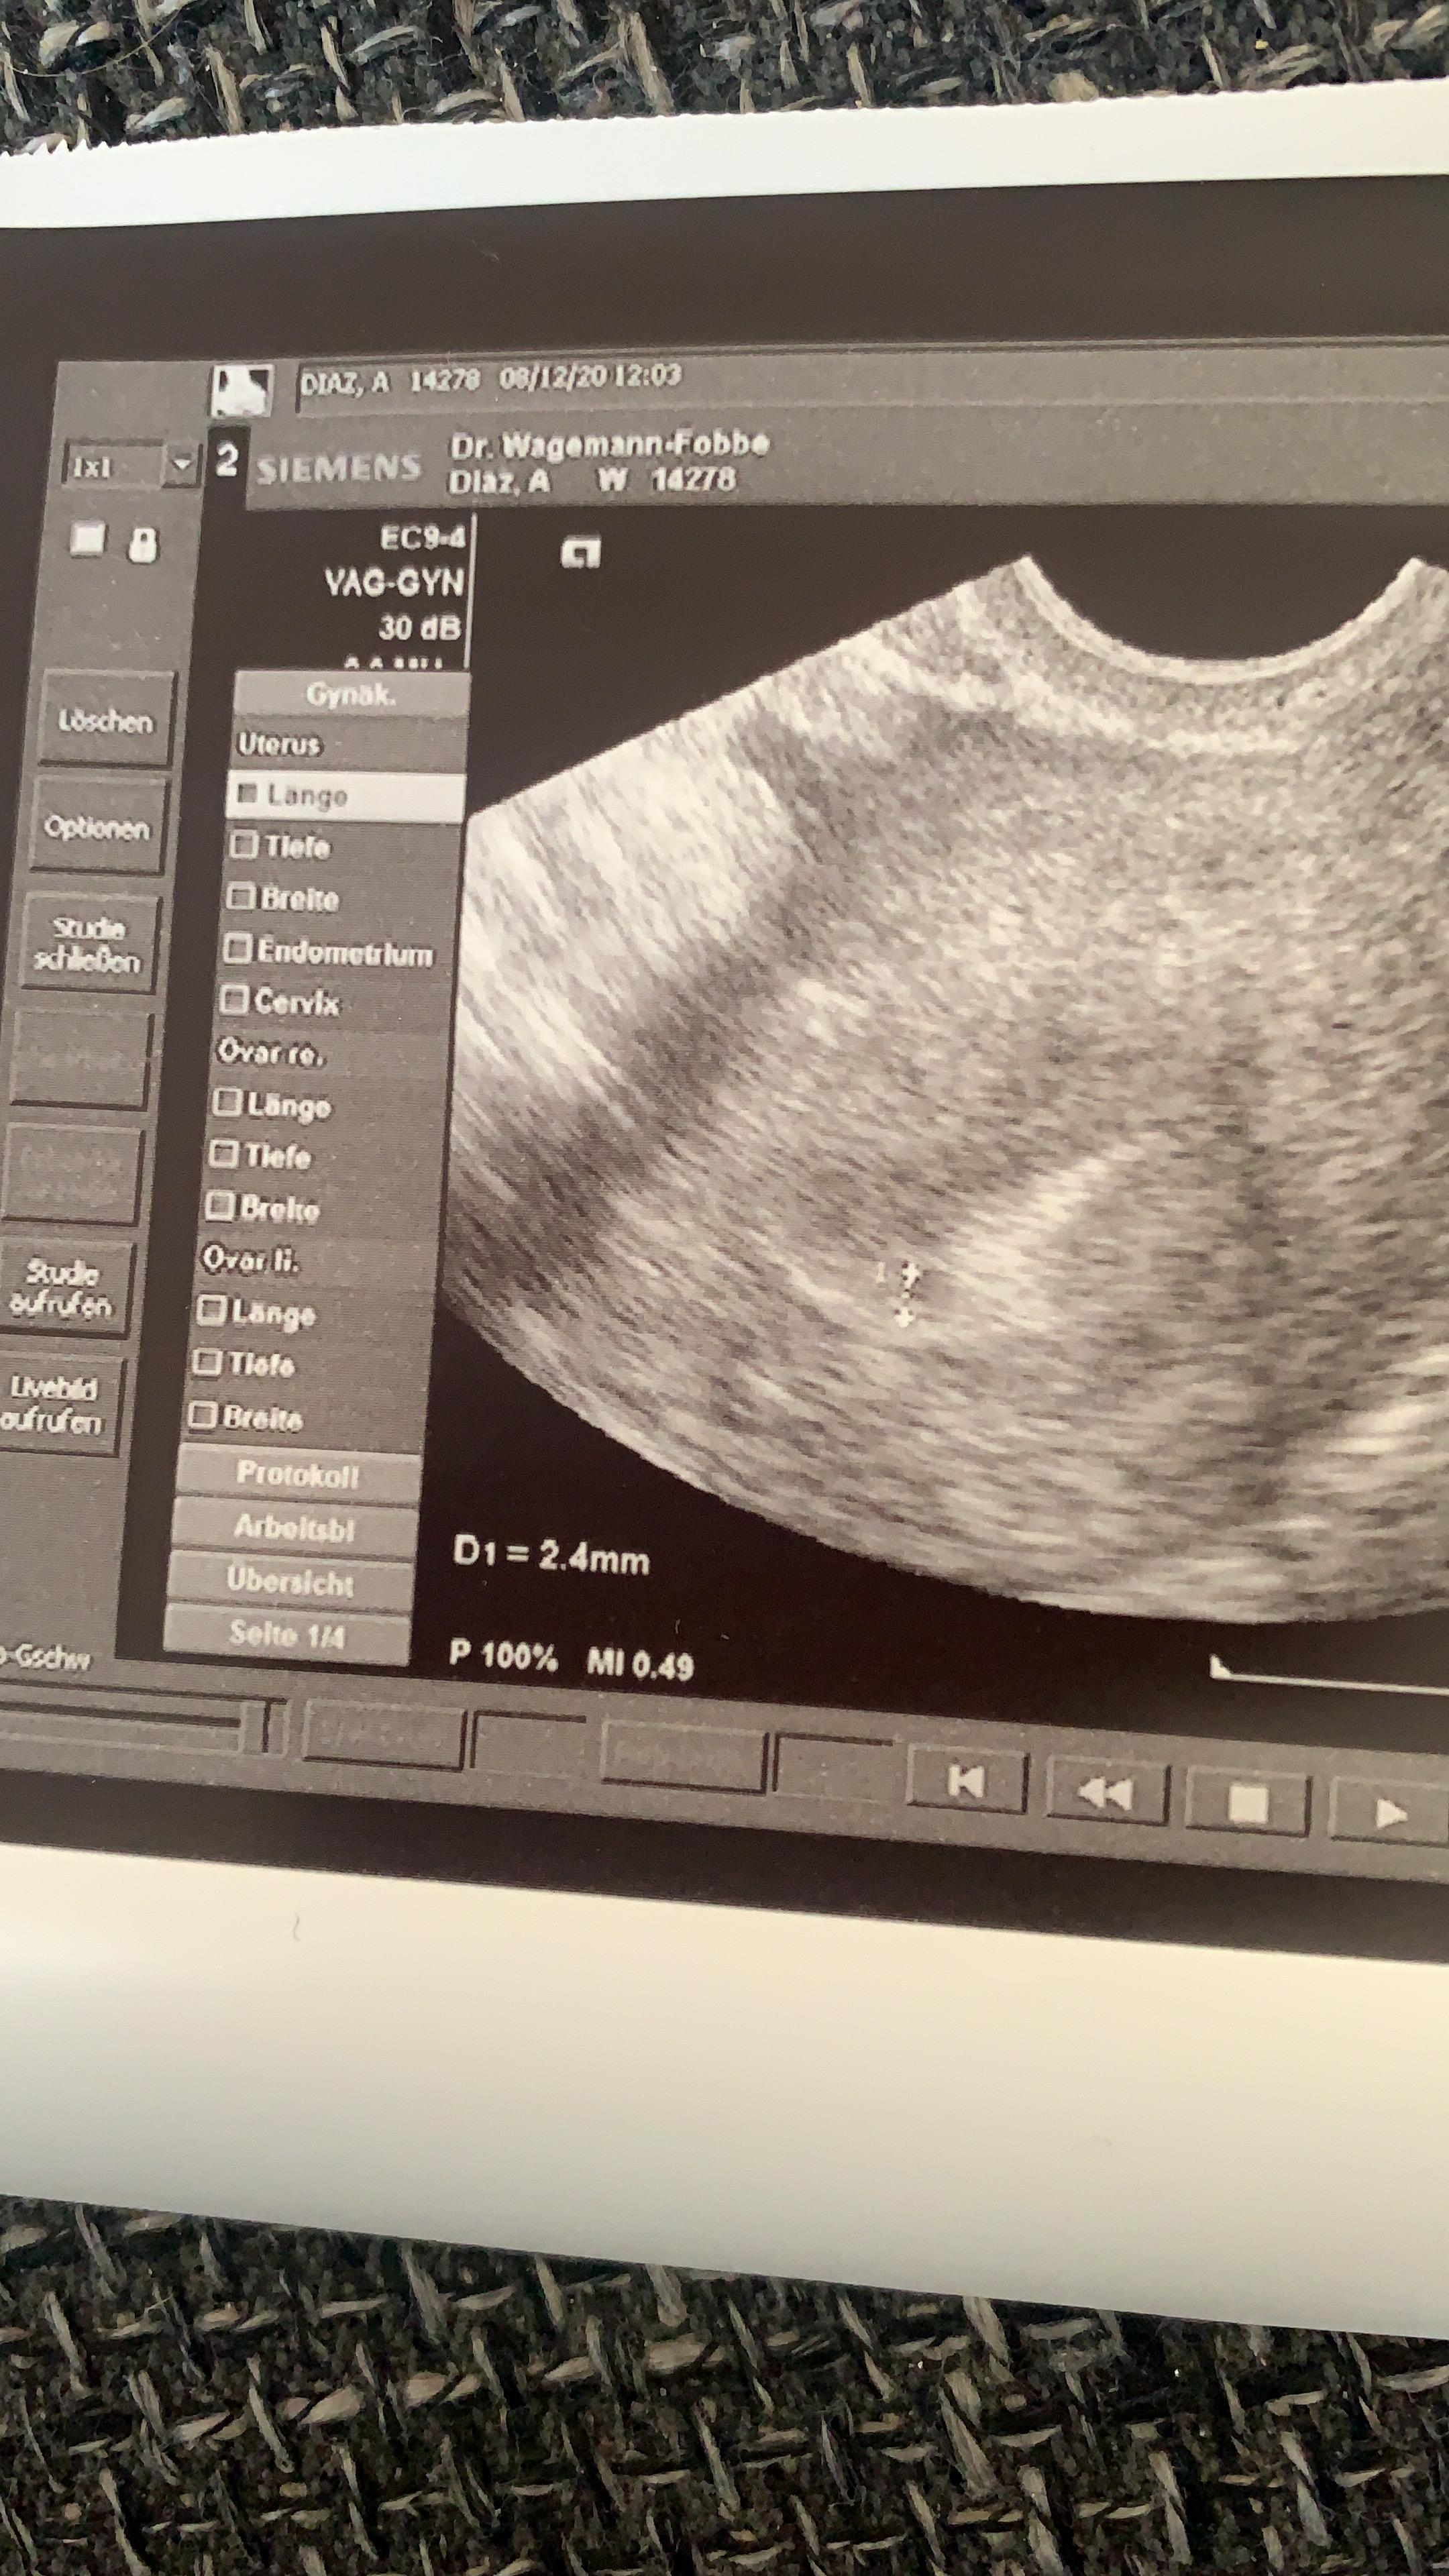

Ultraschall 4 5ssw Gesundheit Und Medizin Schwangerschaft

Ultraschall 4 4 Forum Schwangerschaft Urbia De